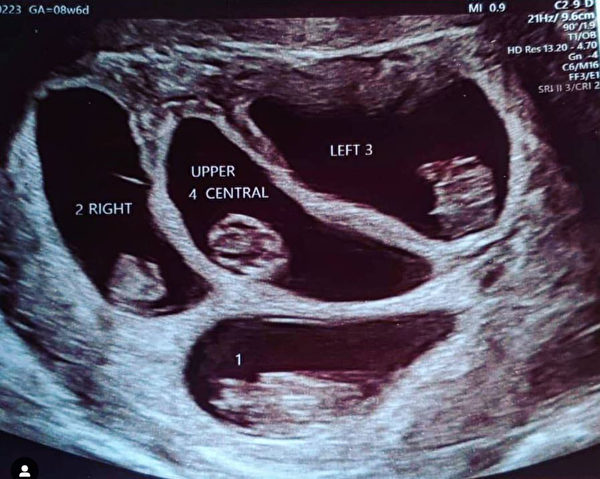

娜塔莉告诉媒体“生活”(That’s Life),“我躺在孕检台上,超声波医师用B超仪为我做检查,我看了一下模糊的屏幕,发现了两个囊。”

纳塔莉欣喜若狂,因为她的家族的确有生双胞胎的家族史。但超声波医师报出的胎儿数目震惊了在场所有的人。她回忆道:“超声波医师一言不发,举起了四个手指。卡恩几乎晕了过去。”